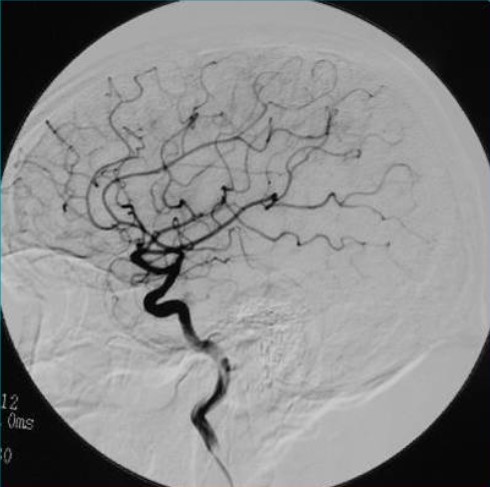

通过该动脉鞘管选用不同导管,在导丝引导下,选进所要显示动脉,注入含碘造影剂,造影剂所经过的血管轨迹连续摄片,通过电子计算机辅助成像为脑血管数字减影造影(DSA),是目前评价脑血管病的“金标准”。